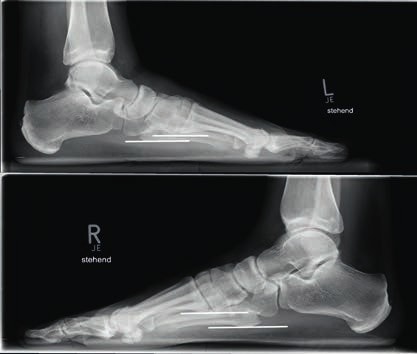

- Bei einer Grad-II-Verletzung findet sich in den Röntgenaufnahmen unter Belastung eine Diastase zwischen dem I. und II. Mittelfußknochen von 2 bis 5 mm. Die Seitenaufnahme des Fußes im Seitenvergleich ist unauffällig (Abb. 3). Im MRT kann eine partielle Ruptur der Bänder nachgewiesen werden. Nicht selten finden sich ab Grad-II-Verletzungen im MRT Ödeme der subchondralen Spongiosa der angrenzenden Gelenkflächen.

- Bei Grad-III-Verletzungen liegt eine Zerreißung der dorsalen und plantaren Anteile des Lisfranc-Bandkomplexes vor. Dies bedingt eine ausgeprägte Instabilität des ersten Strahls. In den belasteten Röntgenaufnahmen ist eine Diastase zwischen dem I. und II. Mittelfußknochen sowie ein Absinken des Längsgewölbes erkennbar. Im Seitenvergleich lässt sich dies am Abstand der plantaren Kortikalis des Metatarsale I in Beziehung zur plantaren Kortikalis des Metatarsale V erkennen (Abb. 4).

Bei Athleten tritt eine Verletzung des Lisfranc-Bandkomplexes typischerweise auf, wenn der Fuß bei gleichzeitiger Plantarflexion und leichter Rotation axial belast et wird 43 44. Die Zerreißung des Lisfranc-Bandkomplexes führt zu einer tarsometatarsalen Dehiszenz mit Dislokation der Metatarsale-II-Basis nach dorsal 45. Nunley und Vertullo (2002) 46 gehen in ihren Untersuchungen davon aus, dass es bei der Grad-I-Verletzung lediglich zu einer Distorsion des Lisfranc’schen Bandes in Verbindung mit einer Verletzung der Gelenkkapsel kommt. Aufgrund des in sich noch stabilen Kapselbandkomplexes finden sich normale Belastungsaufnahmen; die Verletzung der dorsalen Bandanteile lässt sich jedoch kernspintomografisch nachweisen 47. Bei der Grad-II-Verletzung kommt es zusätzlich zu einer vollständigen Zerreißung der dorsalen Bandanteile. Radiologisch zeigt sich dies durch das Auseinanderweichen von Os metatarsale I und II auf den Röntgenaufnahmen unter Belastung. Da die plantaren Kapselbandanteile intakt bleiben, kommt es jedoch zu keinem Absinken des Längsgewölbes in der Seitenaufnahme. Bei Grad-III-Verletzungen liegt eine komplette Zerreißung der dorsalen und plantaren Kapselbandstrukturen mit einem instabilen ersten Tarsometatarsalgelenk vor. Dies zeigt sich radiologisch durch ein Absinken des Längsgewölbes 48.